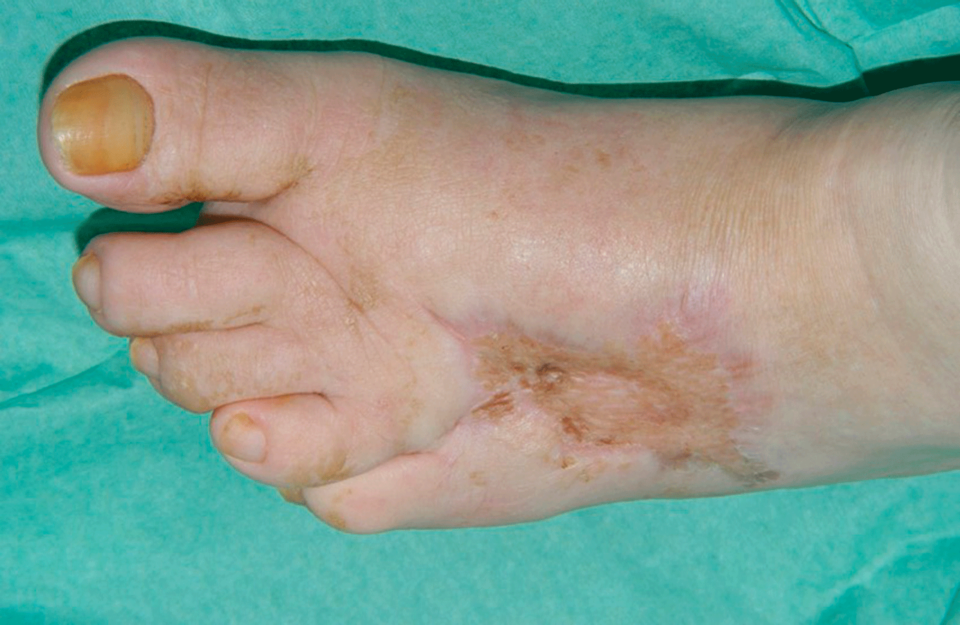

Eine klassische Phlegmone beim diabetischen Fußsyndrom sechs Wochen nach Therapie.

Eine klassische Phlegmone beim diabetischen Fußsyndrom sechs Wochen nach Therapie. © Dr. Axel Mechlin, Hautklinik am Klinikum Nürnberg Nord